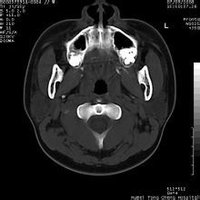

鼻咽部ct軸位平掃(層厚、層距均為5mm),圖像如下:

起源於翼內板,翼突上頜裂和蝶齶孔,主要累及篩竇,蝶竇和顱底。

腫塊引起翼齶窩擴大,壓迫上頜竇後壁,使其彎曲,變形,並向前移位是本病的特徵性表現。